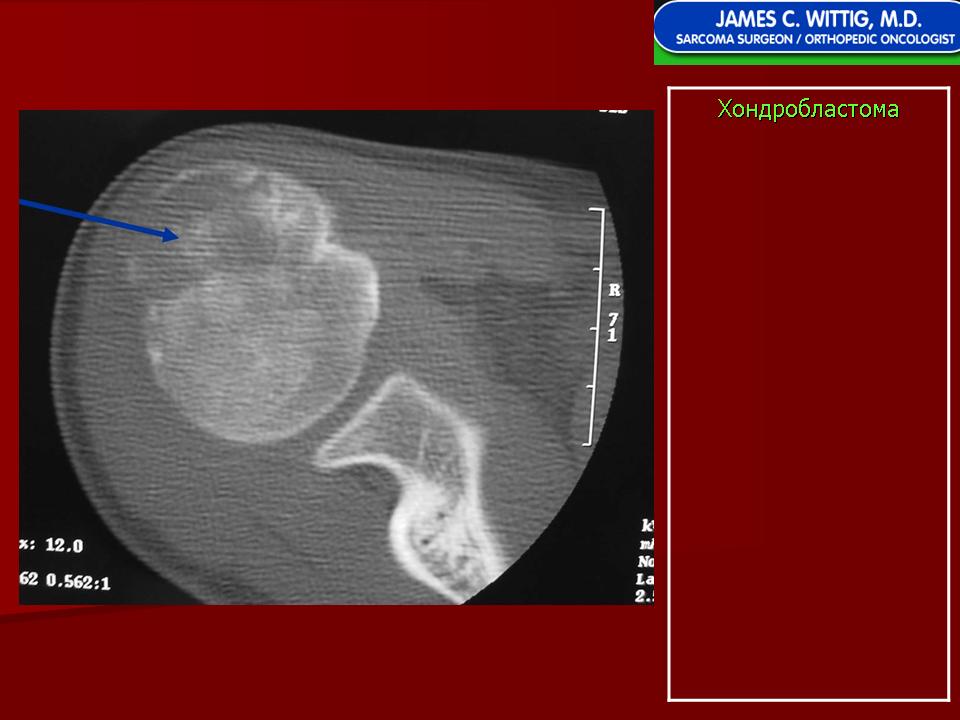

Рентгенологически хондробластома представляет собой сравнительно большой (2-4 см) очаг округлой формы, четко отграниченный от окружающей кости склеротической каймой. На фоне очага в большинстве случаев, но не обязательно определяются плотные включения, напоминающие хлопья ваты.

Рентгенологическая картина. Хондробластома выглядит как небольшой, от 3 до 6 см литический очаг, центрально или эксцентрично расположенный, с четкими контурами, занимающий около половины площади эпифизарной зоны. Хондробластома плоских костей и мелких трубчатых костей больших размеров, может сопровождаться припухлостью мягких тканей, вздутием кости и периостальной реакцией. Распространение процесса на метафизарную зону встречается часто.

Хондробластома — это редкая доброкачественная опухоль, локализующаяся, главным образом, в диафизах и отличающаяся своеобразным клеточным составом. Ткань новообразования представлена овальными, округлыми и веретеновидными клетками, напоминающими незрелые хондроциты (хондробласты). Зрелый гиалиновый хрящ определяется лишь в некоторых опухолях. Возраст больных варьирует от 3 до 72 лет. Мужчины поражаются в два раза чаше женщин. Пациенты предъявляют жалобы на боли в течение нескольких месяцев или лет, у некоторых больных определяются внутрисуставной выпот, припухлость и ограничение движений. Наиболее типичная локализация опухоли — проксимальные эпифизы плечевой и большеберцовой костей, а также дистальный эпифиз бедренной кости. У 20 % больных опухоль развивается в плоских или коротких трубчатых костях, преимущественно в пяточной и таранной. Изредка поражаются кости лицевого черепа, в том числе височная. При рентгенологическом исследовании видна типичная картина злокачественной опухоли остеолитического типа. В большинстве случаев новообразование выходит за пределы эпифиза и распространяется на метафиз. На фоне остеолиза обнаруживаются рассеянные участки обызвествления в виде пунктирных линий, а также разреженный трабекулярный рисунок. Хондробластома, как правило, не выходит за пределы кости, но изредка проникает в полость сустава. В процессе роста опухоли иногда возникает вторичная аневризматическая костная киста. Хондробластома — это доброкачественная опухоль, поэтому для ее лечения используется кюретаж с последующей костной пластикой. У некоторых больных в течение 3 лет после этого возникает рецидив, для лечения которого также используется кюретаж или же резекция опухоли. Примерно 1 % хондробластом отличается агрессивным местным ростом и метастазирует в легкие, причем метастазы могут выявляться спустя многие годы после обнаружения первичного узла. Некоторые хондробластомы прорастают в окружающие мягкие ткани, но при этом не метастазируют. Описаны случаи малигнизации этого новообразования после лучевой терапии с формированием фибро-или остеосаркомы. Макроскопический вид хондробластомы варьирует. Обычно опухоль состоит из зернистой ткани желтовато-серого или буровато-серого цвета, в которой определяются кровоизлияния и аневризматические кисты. Видны также голубовато-серые участки, соответствующие хондроидному матриксу. Точечные желтоватые вкрапления соответствуют очагам обызвествления или реактивного остеогенеза. По периферии опухоли определяется поясок склерозированной костной ткани. Микроскопическая картина зависит, главным образом, от количества хондроидного матрикса, продуцируемого опухолевыми клетками, а также от распространенности некроза, наличия аневризматических кист. Обращает на себя внимание клеточный полиморфизм. Наибольшее число клеток составляют хонлробласты с четкими контурами, в которых определяются округлые или овальные ядра, окруженные зоной просветления. Ядра клеток расщепленные, с глубокими инвагинациями и вдавлениями. Ядерный хроматин выглядит мелкораспыленным или в виде скоплений неправильной формы. Число фигур митоза в опухоли обычно невелико, и они определяются только в 75 % случаев. Лишь изредка это число превышает 4 на 10 полей зрения при большом увеличении микроскопа. Атипичный митоз не встречается. Клеточный атипизм обнаруживается лишь у 20—30 % хондробластом. Обычно это крупные неправильной формы клетки с гиперхромными ядрами. По-видимому, их наличие не является неблагоприятным прогностическим признаком. В некоторых участках границы между хондробластами неотчетливые, и общая картина приобретает вид синцития. Наряду с округлыми элементами в опухоли встречаются и веретеновидные клетки, которые образуют гнездные скопления или же равномерно вкраплены между типичными клетками. Встречаются также многоядерные клетки, часть которых очень похожи на крупные остеокласты. Все вышеописанные клетки дают положительную реакцию на SlOO-протеин, нейронспецифическую энолазу и виментин.